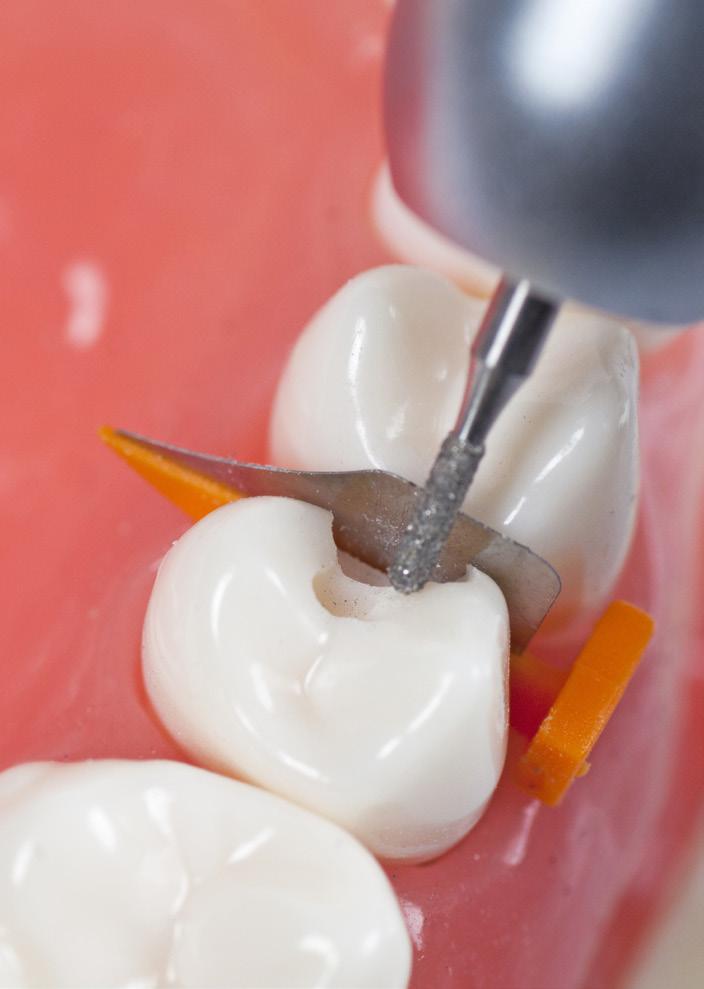

CMS Root n’ screw brush er roterende, engangs depurasjonsbørster utviklet i samarbeide med prof. dr. Claudio Mongardini fra Italia. For rene overflater og implantater.

Brukes ved 200 til 600 omdreininger på vinkelstykket. Børstefibrene er laget av nylon. Finnes i to størrelser, gult skaft (D2) med børstediameter på 2mm, og oransje skaft (D3) børstediameter på 3mm. Lengden på begge er 37mm. Børstene kan brukes i større, åpne lommer og i furkaturer. Børstene kan autoklaveres før bruk om ønskelig.